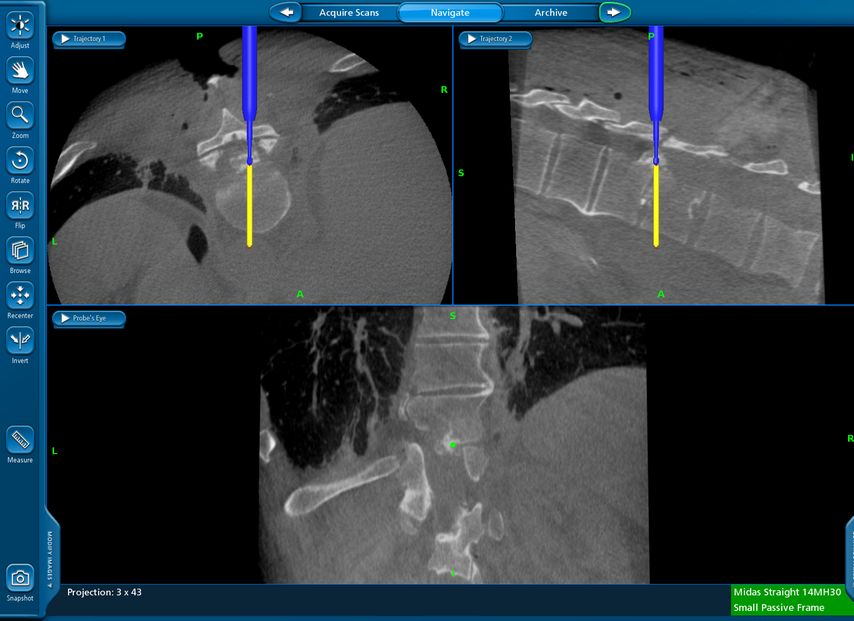

TLIF über Mittellinienzugang mit Schrauben in „cortical bone trajectory“. Bei der 63-jährigen Patientin bestand eine degenerative Spondylolisthese Meyerding Grad I mit Facettengelenkszysten und Wirbelkanalstenose (Abb. 8). Klinisch bestanden Lumboischialgien mit Ausstrahlung dem Dermatom L5 bds. entsprechend. Es wurde ein Mittellinienzugang durchgeführt und zuerst wurden navigierte Schrauben in „cortical bone trajectory“ platziert (Abb. 9). Anschließend erfolgten eine Facettektomie L4/5 links und eine Dekompression des Wirbelkanals. Abbildung 10 zeigt, dass der Hautschnitt aufgrund der mittelliniennahen Schraubenköpfe klein gehalten werden kann. Klinisch wurden die lumbalen Schmerzen wie ausstrahlende Beschwerden 1 Jahr postoperativ annähernd vollständig behoben, die korrespondierende Röntgenkontrolle ist in Abbildung 11 dargestellt.